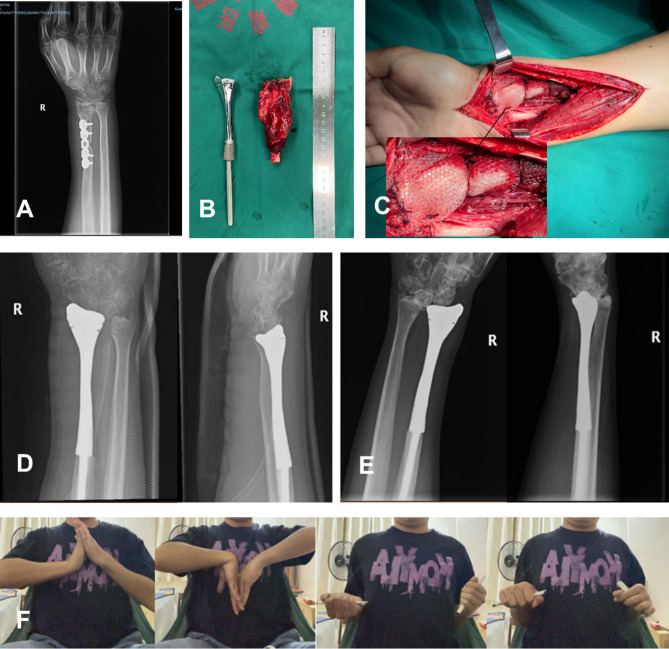

22岁男性病例研究。(A)术前X光片;(B)肿瘤切除及假体植入术中图像;(C)术中放置包裹在网状移植物中的3D打印金属假体;(D)术后X光片(3天,前后位和侧位视图);(E)术后X光片。图片由广西医科大学第一附属医院提供